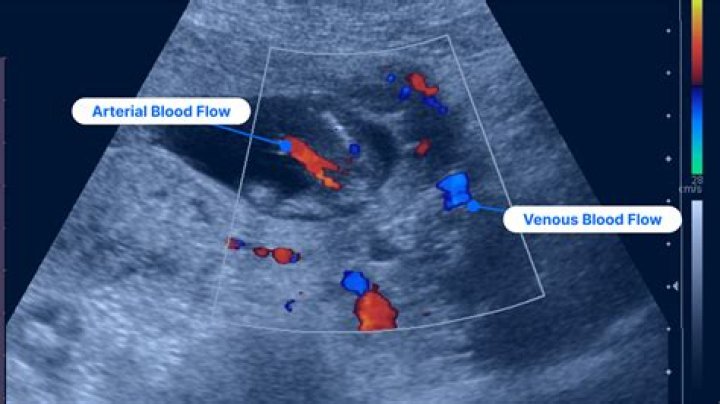

What do colors mean in ultrasound?

By definition, flow towards the transducer is depicted in red while flow away from the transducer is shown in blue. Different shades of red and blue are used to display velocity. Lighter shades of color are assigned to higher velocities.

What do red and blue colors mean on ultrasound?

Vessels in which blood is flowing are colored red for flow in one direction and blue for flow in the other, with a color scale that reflects the speed of the flow. Because different colors are used to designate the direction of blood flow, this Doppler technique simplifies interpretation of the ultrasound data.